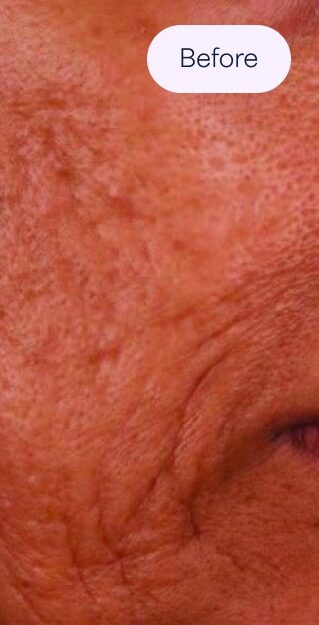

Acne Scars

Deep pits (usually less than 2mm across).

Extend into the skin, giving the skin an appearance of having been punctured by an ice pick.

Angular scars with sharp vertical edges.

May be shallow or deep.

Most often found on the cheeks and temples.

Caused by damage under the surface of the skin.

Give the skin a wave-like appearance.

Tend to be wide and shallow.

How It Works

- Mechanically breaks down scar tissue.

- Activates cellular enzymes known as matrix metalloproteinases, or MMPs.

- Remodels scar tissue through the proper deposition of collagen and elastin.

- Addresses the red and purple discolouration associated with acne scars by increasing blood flow.

- Addresses the brown discolouration, or post-inflammatory hyperpigmentation (PIH), associated with acne scars by stimulating the skin’s natural growth factors.

Female, Procedures: 6. Photos courtesy of: Cathy A. Presnick, Licensed Aesthetician; A Perfect Complexion, LLC, Melbourne, FL